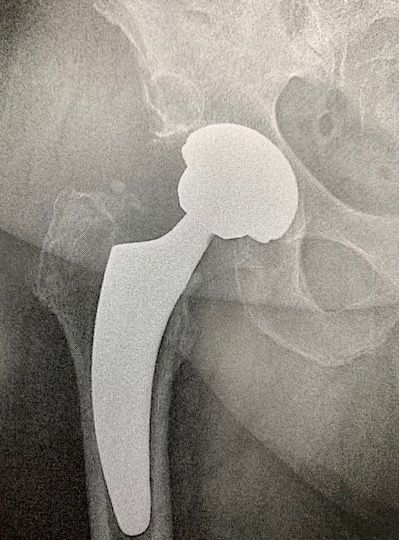

4. Value of a short stem in cases of sequelae of osteotomy, femoral curvature or narrow femur

While the initial goal is to restore the preoperative anatomy as closely as possible, it may have undergone changes due to fracture malunions, pathologies or surgical interventions, especially osteotomy, making it complex to open the femoral shaft. Sometimes, it is simply the native morphology of the femur that is unusual and requires technical consideration from the surgeon. It may in these cases prove very useful to choose a short stem (Figs 7 and 8). These are less common indications but they are worth mentioning.